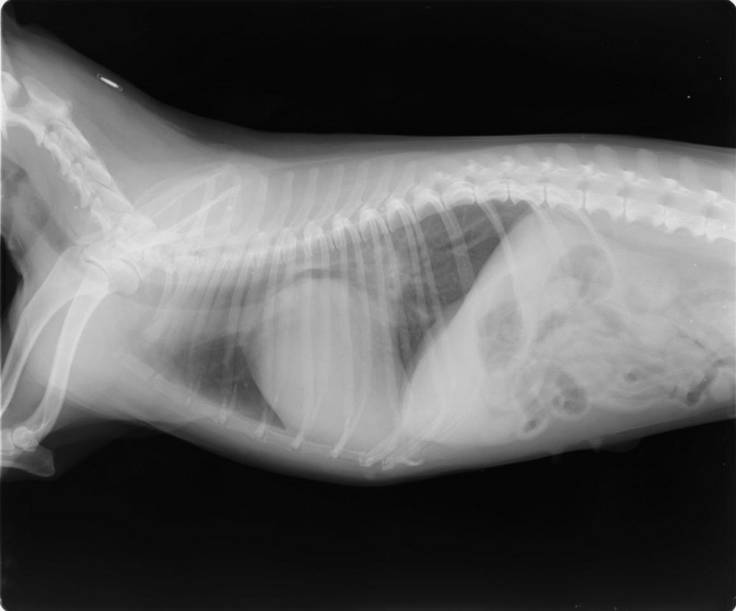

▽レントゲン写真

※かかりつけの動物病院からの掲載許可をいただいています。

心臓が大きくなり気管を下から押し上げています。